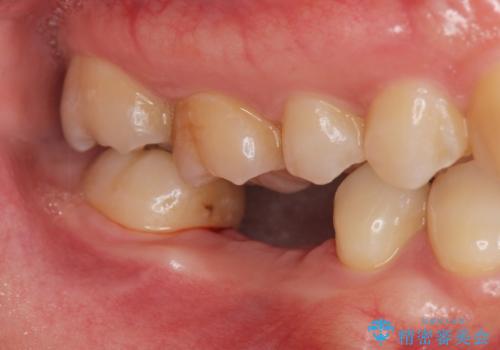

根だけ残った歯は、破折があり急性の炎症が認められ抜歯が必要な状態です。

抜歯後は、前後の歯を削らずにしっかりと咬合力を回復できるインプラント治療を選択されました。

虫歯の放置により吸収してしまった骨も造成を行うことでインプラント周囲環境をしっかりと整えています。